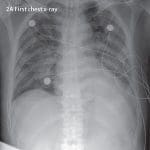

For the purposes of this tutorial, I thought to explore X-ray images as doctors frequently use X-rays and CT scans to diagnose pneumonia, lung inflammation, abscesses, and/or enlarged lymph nodes.

Since COVID-19 attacks the epithelial cells that line our respiratory tract, we can use X-rays to analyze the health of a patient’s lungs.

And given that nearly all hospitals have X-ray imaging machines, it could be possible to use X-rays to test for COVID-19 without the dedicated test kits.

A drawback is that X-ray analysis requires a radiology expert and takes significant time — which is precious when people are sick around the world. Therefore developing an automated analysis system is required to save medical professionals valuable time.

Our COVID-19 patient X-ray image dataset

The COVID-19 X-ray image dataset we’ll be using for this tutorial was curated by Dr. Joseph Cohen, a postdoctoral fellow at the University of Montreal.

One week ago, Dr. Cohen started collecting X-ray images of COVID-19 cases and publishing them in the following GitHub repo.

Inside the repo you’ll find example of COVID-19 cases, as well as MERS, SARS, and ARDS.

In total, that left me with 25 X-ray images of positive COVID-19 cases (Figure 2, left).

To do so, I used Kaggle’s Chest X-Ray Images (Pneumonia) dataset and sampled 25 X-ray images from healthy patients (Figure 2, right). There are a number of problems with Kaggle’s Chest X-Ray dataset, namely noisy/incorrect labels, but it served as a good enough starting point for this proof of concept COVID-19 detector.

After gathering my dataset, I was left with 50 total images, equally split with 25 images of COVID-19 positive X-rays and 25 images of healthy patient X-rays.